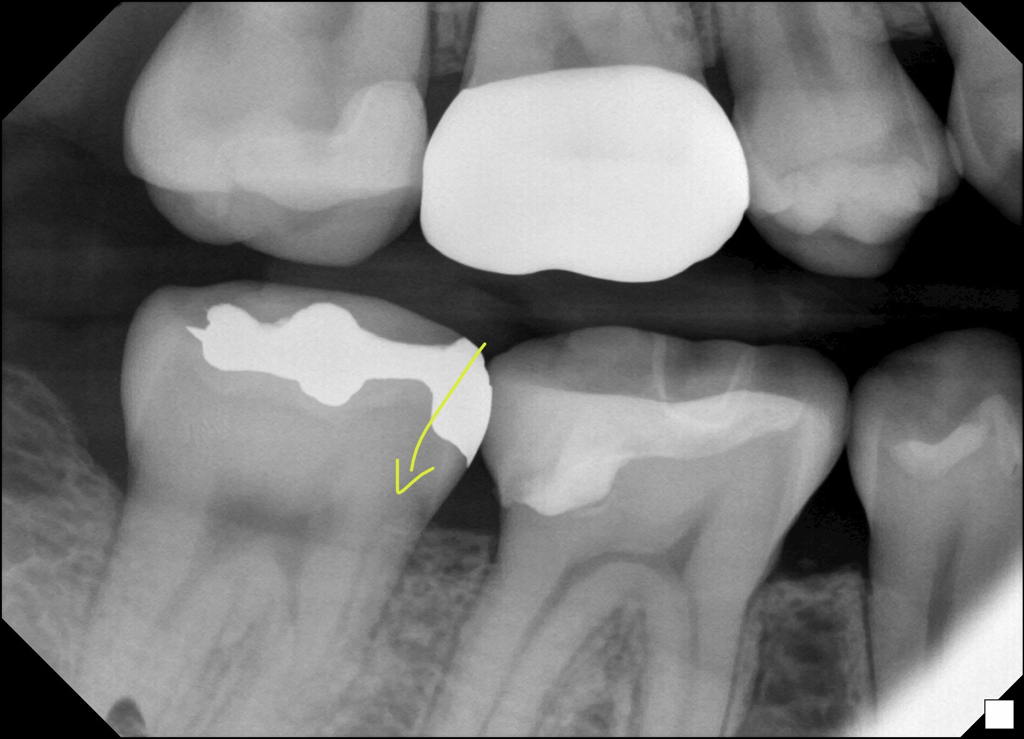

치근단 사진 자세히 보니 크랙같은 선이 보이는데.. 크랙일까요? 보존과 전문의 선생님은 보시고 아무 말씀 안하시던데.. 크랙 증상인데 크랙이 아닐 경우도 있나요?